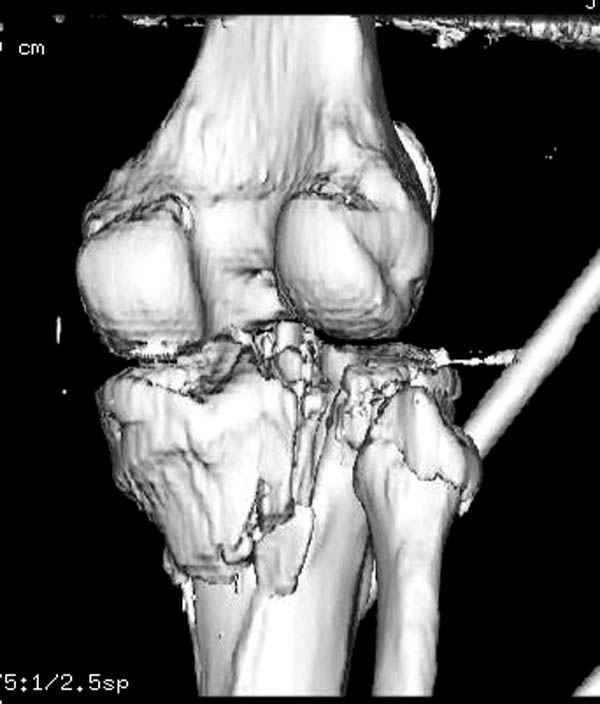

Здесь как раз тот случай, когда результат зависит не только от мастерства хирурга, но и от наличия современных методов исследования. Например, КТ которая поможет рассчитать направления шурупов и установку импланта. Кроме этого, поможет определиться с доступом.

На представленных предоперационных срезах КТ огромный задне-медиальный фрагмент расположен больше кзади, чем медиально. Для планирования, кроме поперечных срезов, надо ориентироваться на корональные срезы, которые укажут топографию верхушки медиального фрагмента.